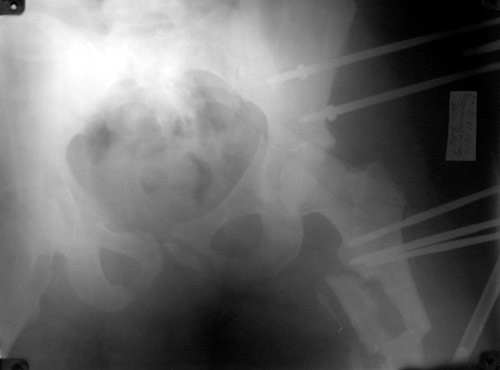

То, что получилось в приложении. Стоит ли дальше тянуть головку винтами или низводить проксимальный отломок по оси?

Уважаемый Борис! Я не имел возможности ознакомиться с рентгенологической картиной сразу после травмы. Имею картинку на данный момент (Ваше приложение). Считаю, что Вы имеете право оставить всё в имеющемся состоянии, но желательна дополнительная дистракция по оси шейки бедренной кости. Далее стабилизировать аппарат. Артроз больному обеспечен, сроки наступления его декомпенсации известны только аллаху.

С> То, что получилось в приложении.

Можно только порадоваться за пациента и врачей, положение отломков значительно улучшилось. Может быть, удастся добиться "вторичной конгруэнтности" даже при сохраняющемся диастазе на уровне перелома. Из того, что видно - стержней в тазу маловато, лучше бы зацепиться за гребни подвздошных костей (по 3-4 стержня), тогда можно будет пациента и поднять на костыли.

Возможно, и то, и другое. По одной прямой проекции ситуацию не оценить - желательно сделать косые проекции (Judet) левой вертлужной впадины, на которых будет видно, конгруэнтна ли головка со сводом, не надо ли подвинуть ее кпереди или кзади.

По бедру - ось (по одной проекции) и длина восстановлены. Непривычно выглядит стержень с медиальной стороны, мы обычно обходимся только

наружной полуокружностью бедра. Если аппарат здесь предполагается как окончательный фиксатор - похоже, это надолго...

На первый взгляд репозиция вертлужной впадины не плохая, однако следует сделать проекционные снимки по Judet, а вот аппрат конечно подкачал, да и больного жалко. Былобы красиво сейчас после рентген-контроля перкутанно ппровести стягивающие винты через перелом вертлужной впадины из подвздошной в лобковую и из седалищной в подвздошную. А бедро заштифтовать, а потом снять аппарат и отпустить больного, передний отдел возможно фиксировать АВФ.

Подумайте - помечтайте все закрыто!!!